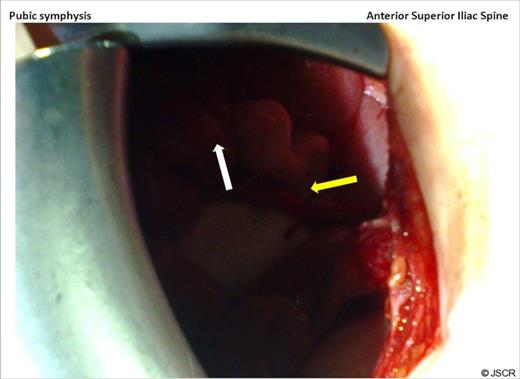

At laparotomy, looking down at the pelvis through a right iliac fossa transverse incision, caecum is seen (white arrow) and the appendix with its tip (yellow arrow) can be seen lying in the inguinal canal.